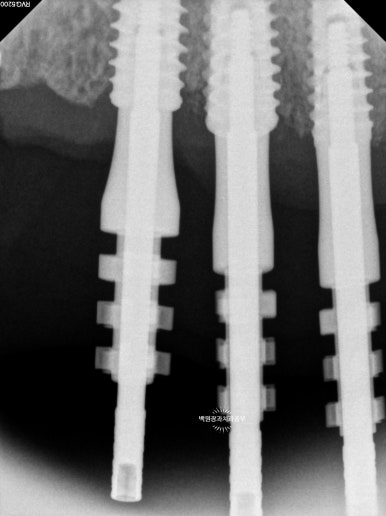

기공소에서 맞춤형 지대주 (custom abument)와 임시치아를 만들어 옵니다.

약 2주간의 기다림 끝에 기공소에서 맞춤형 지대주 (custom abutment)와 임시치아를 만들어 왔어요!!!

자~ 맞춤형 지대주와 임시치아가 무엇인지 좀 더 자세히 살펴봅시다.!!

임플란트는 조립식으로 되어 있습니다.

제가 임플란트 1차수술 때 잇몸뼈 안에 위치시킨 것은 고정체 (fixture)라고 불립니다. 뼈 속에 위치한 고정체에 기둥을 연결하게 되는데, 그 기둥이 바로 지대주 (abutment)입니다. 그 지대주에 치아 모양의 크라운을 붙이게 되지요. 아!! 어렵죠? 눈으로 보시면 이해가 잘 될겁니다.

제가 사용했던 것은 '맞춤형 지대주 (custom abutment)' 입니다. 다른 종류로 '기성 abutment'도 있습니다.

맞춤형 지대주가 기성 지대주보다 더 좋은 것입니다.